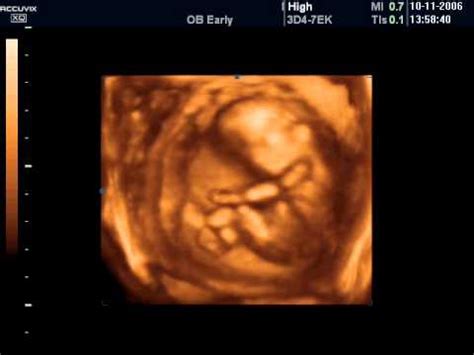

În ultimii ani, ecografia a început să fie folosită din ce în ce mai des ca metodă de diagnostic, fiind considerată o metodă neinvazivă pentru organismul uman. De asemenea, această metodă de diagnosticare a evoluat foarte mult și din punct de vedere tehnic, în prezent putându-se realiza în mod curent ecografii 4D, în care sunt observate, pe lângă caracteristicile morfologice ale organismului, și cele funcționale. O astfel de ecografie oferă o imagine în mișcare a fătului și poate oferi uneori mai multe detalii decât o ecografie bidimensională.

La sfârșitul săptămânii a 7-a, embrionul măsoară 2-3 cm, cam cât o roșie mică. Organele interne se formează, micuțele membre încep să se miște, imperceptibil, iar organele genitale externe sunt prezente, deși nu sunt distincte. Urechile se formează, iar embrionul se dezvoltă rapid. Fața capătă aspect uman, iar pleoapele sunt închise bine peste ochi. Embrionul începe să miște mânuțele și piciorușele, mișcare vizibilă la ecografie.